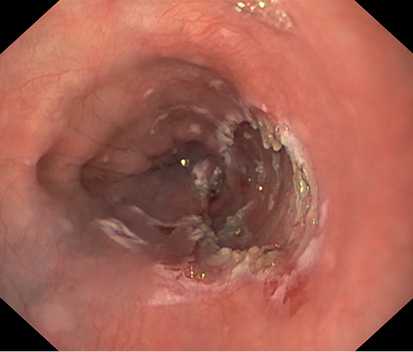

Образование извлечено с помощью эндоскопической петли и направлено на гистологическое исследование. На месте удаленного образования определялся дефект слизистой оболочки до 2 см в диаметре без визуальных признаков повреждения мышечного слоя стенки пищевода (рис. 5). В послеоперационном периоде пациенту рекомендована щадящая диета с исключением грубой пищи, проведена антисекреторная терапия ингибиторами протонного насоса. В 1-е сутки после операции ESD выполнено рентгенологическое контрастное исследование с целью исключения перфорации стенки пищевода с учетом первого опыта диссекции. Затекания контрастного вещества за контуры пищевода не отмечалось (рис. 6, 7).

Рис. 5. Дефект слизистой оболочки пищевода. Фото авторов.

Пациент выписан в удовлетворительном состоянии на 3-и сутки после операции. Для оценки динамики рубцевания и исключения рубцового сужения просвета пищевода на уровне диссекции на 5-е сутки выполнена ЭГДС, при которой выявлено, что дефект слизистой оболочки пищевода покрыт фибрином (рис. 8).

Рис. 8. Дефект слизистой оболочки пищевода, покрытый фибрином. Фото авторов.